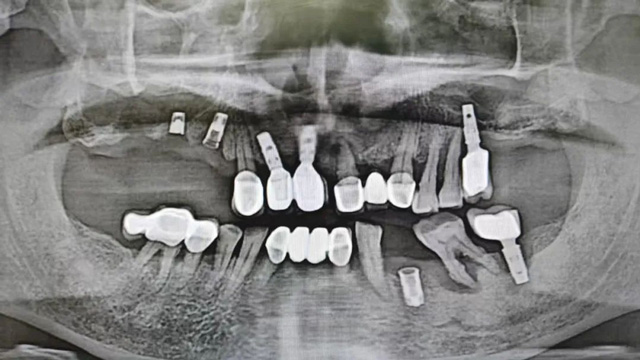

上半口即刻種植后全景片

手術中拆除的種植體

“我們通過上半口即拔即種、即刻修復治療,將他上面殘留的種植體拆除,同時拔掉無法保留的牙齒,手術同期埋入6顆種植體,術后佩戴了臨時牙冠。由于骨量不好,有3顆種植體采用傾斜植入,1顆做了上頜竇提升植入。”